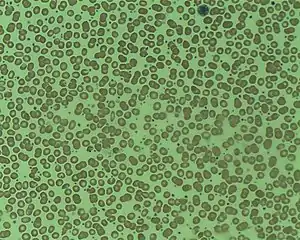

Essential thrombocythemia (ET) is a rare chronic blood cancer (myeloproliferative neoplasm) characterised by the overproduction of platelets (thrombocytes) by megakaryocytes in the bone marrow.[1] It may, albeit rarely, develop into acute myeloid leukemia or myelofibrosis.[1] It is a type of myeloproliferative neoplasm (blood cancers) wherein the body makes too many white or red blood cells, or platelets).[1]